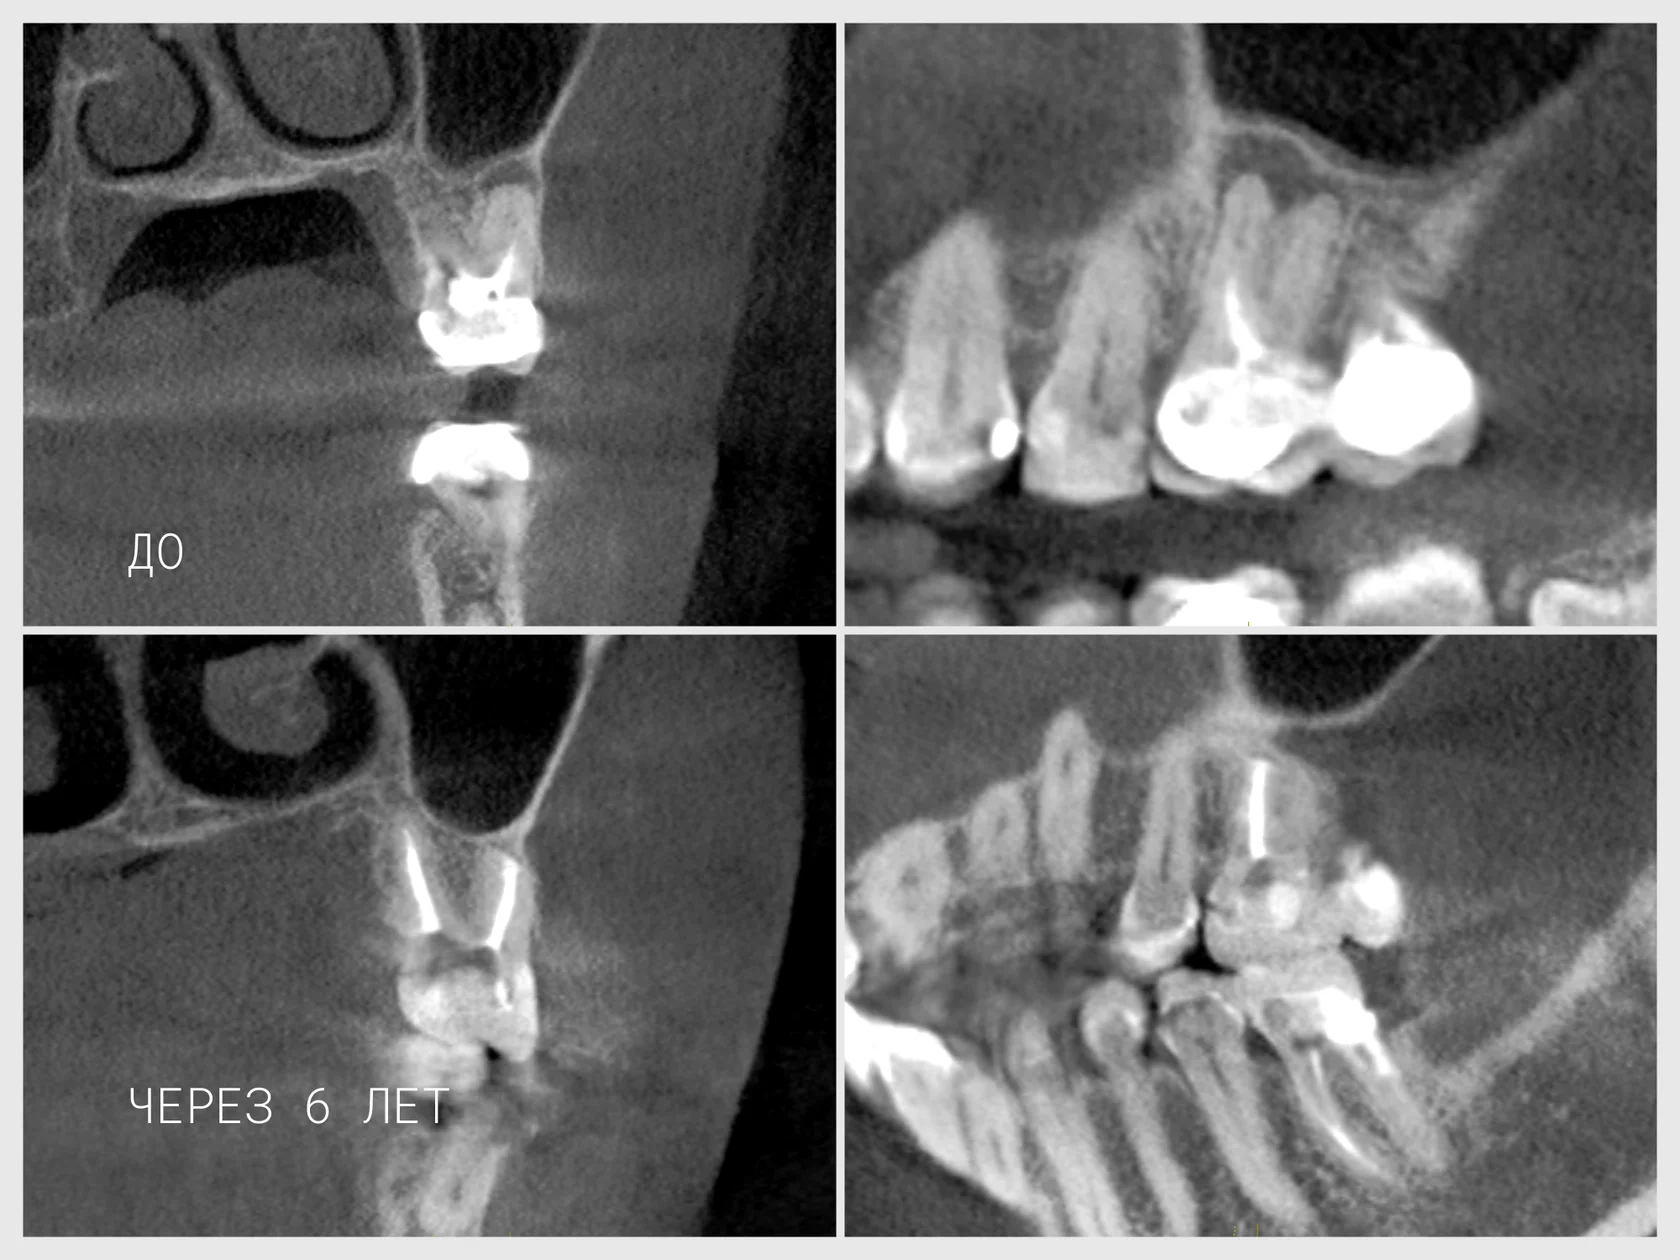

Зуб 2.6 (верхний правый первый моляр) имел воспалительный процесс в области щечных корней. На КЛКТ-снимках видна характерная картина:

- Деструкция костной ткани вокруг верхушек щечных корней

- Расширение периодонтального пространства

- Признаки хронического воспаления

- Зуб был ранее подвергнут эндодонтическому лечанию, но воспаление не разрешилось

Долгосрочный результат: КЛКТ через 6 лет

Контрольный снимок через 6 лет показывает:

- Полное восстановление костной ткани в области резецированных верхушек

- Отсутствие деструкции — новая костная ткань заполнила дефект

- Стабилизация воспалительного процесса — нет признаков рецидива

- Долгосрочная жизнеспособность зуба — зуб продолжает естественно функционировать

- Отсутствие признаков периодонтита — воспалительный процесс полностью разрешился

Этот результат доказывает, что резекция верхушки корня — это не просто удаление поражённой ткани, а создание условий для биологического заживления и восстановления костной ткани.